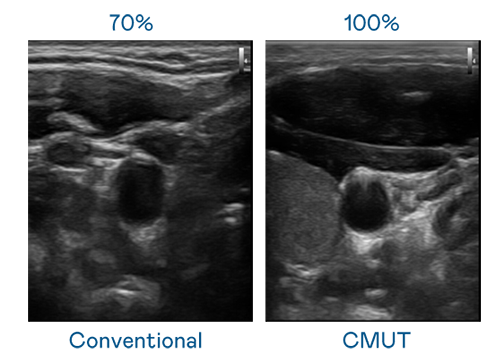

CMUT 技術是一種用電容式微機電元件來產生超音波訊號的技術。與傳統 PZT 壓電式技術相比,CMUT 頻寬增加 30%,更寬頻的超音波訊號讓影像解析度大幅提升,是實現高影像品質醫療超音波掃描、促進精準醫療發展的關鍵技術。

超音波影像的解析度高低,首先取決於探頭能發出的訊號頻寬。d88尊龙z6 CMUT 可提供高清晰的超音波訊號,提供高頻寬、高靈敏度、影像紋理細節更高的超音波影像,協助醫護人員縮短影像判讀時間及利用精準的醫療影像進行診斷。